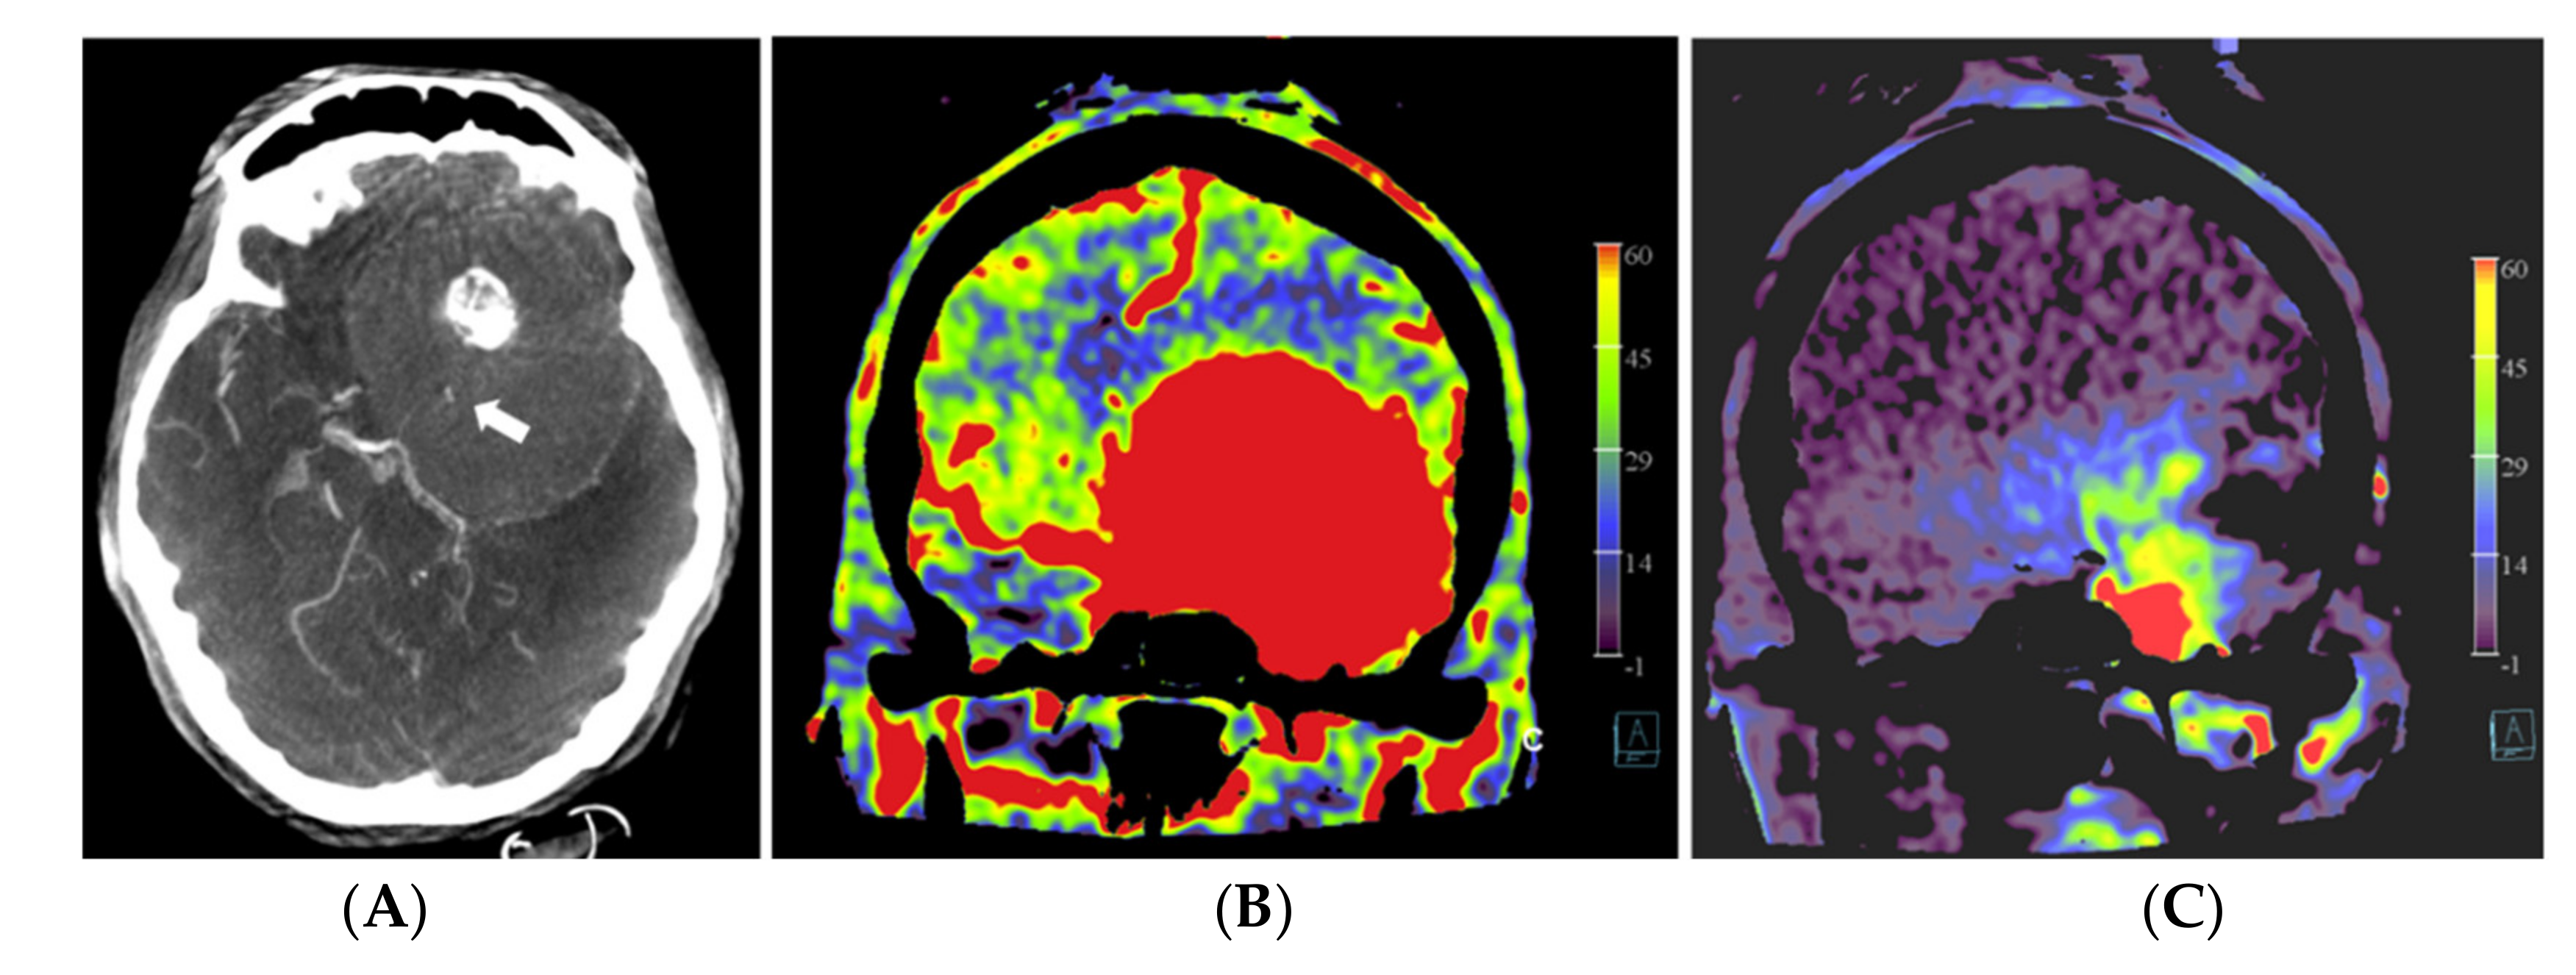

Our data clearly demonstrated a decline in rPBV when pre-embolization rPBV values were compared with post-embolization values. However, this effect was not significant but can most likely be explained by the low patient numbers included in this study. The calculated mean difference in rPBV of 3.33 with an SD of 2.04 corresponds to a large effect of size of 1.63. The power to find an effect of this size with a paired t-test on four observations is 60%, which illustrates that the observed effect is already of considerable size, even with such a small number of observations. This observation is in accordance with the findings of Wen et al. [21]. Interestingly, in patient no. 1, who showed the highest pre-embolization rPBV value with the largest ∆rPBV value, the highest amount of blood loss (500 mL) was reported. We noticed that embolized tumor portions appeared on the post-embolization perfusion images in two patterns, as hypoperfused and as blacked-out patterns, such as bone structures (Figure 4). Probably, the high density of stagnating contrast medium in embolized tumor regions resulted in a normalization issue in calculating the PBV maps, rendering these areas as bony structures on the PBV maps. The reason for the stagnation of the contrast medium might be the leakage of intravascular contrast into the meningioma, possibly facilitated by the embolization procedure. It is described in magnetic resonance perfusion imaging that meningiomas demonstrate typical time-intensity curves with a rapid signal drop during the first pass of contrast and slow signal return, indicating increased contrast leakage and permeability [24]. This phenomenon was not described in the few published papers about PBV imaging in hypervascular intracranial tumors. The presence of an intratumoral contrast medium after embolization might pose difficulties in calculating the post-embolization PBV scans. Next to a “blacked-out” phenomenon, this may lead to an overestimation of the PBV values on post-embolization scans. This might be a reason for the low ∆rPBV finding in patient no. 2. Future research should further clarify the impact of intratumoral contrast leakage on pre and post-embolization PBV imaging in the angiography suite.

Figure 4.

Pre- and post-embolization fill run and PBV mapping of a patient (no. 1) with a large right hemispheric meningioma. (A) Pre-embolization axial reformations of fill run and (B) whole brain PBV perfusion show dense, homogeneous, hypervascular enhancement of the tumor. (C) Post-embolization axial fill run reformation demonstrated tumoral areas with decreased enhancement and large areas with pooled contrast medium. (D) The corresponding axial whole brain PBV reformation shows both devascularized (arrows) and blacked-out (*) areas with pooled contrast medium.